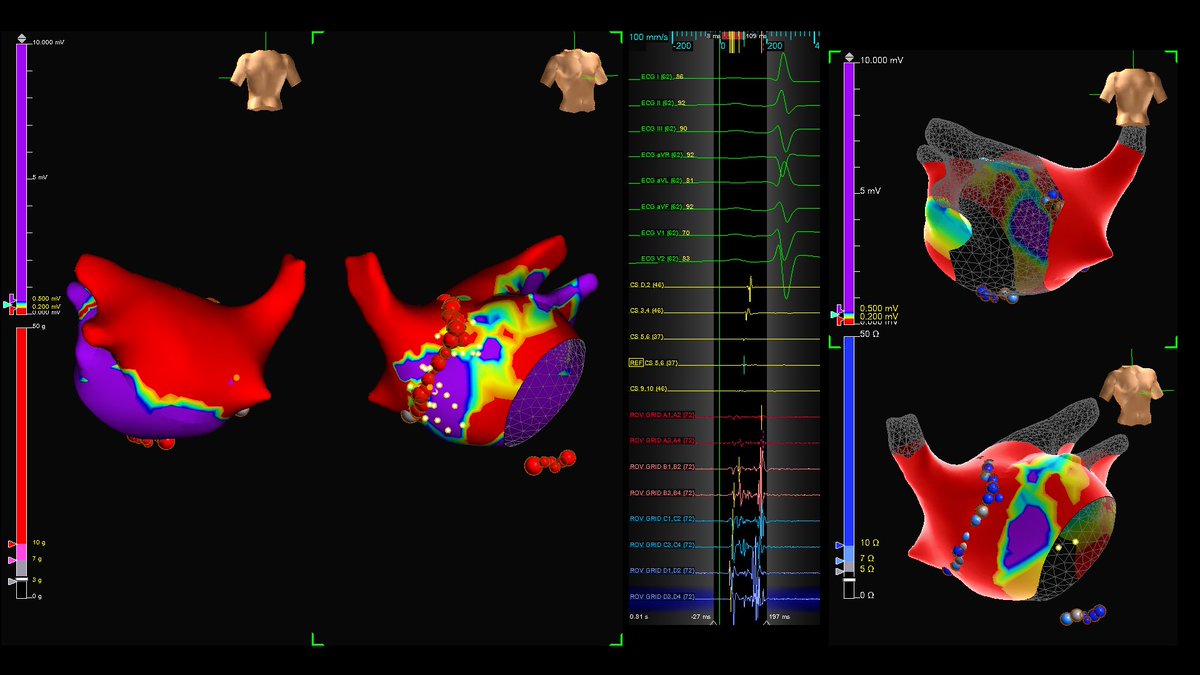

Cryo & RF for PVI + PW + CTI in 2021. AF cardioverted, SR mapped, Voltage with Fractionation map highlighting RPV antrum ablated. Veins and Posterior Wall remain isolated, CTI assessed conduction leak at annulus. D Randy Jones #PMA #TactiFlex

Cryo &amp; RF for PVI + PW + CTI in 2021.

AF cardioverted, SR mapped, Voltage with Fractionation map highlighting RPV antrum ablated.

Veins and Posterior Wall remain isolated, CTI assessed conduction leak at annulus.

<a href="/EPS_PDX/">D Randy Jones</a>

#PMA #TactiFlex